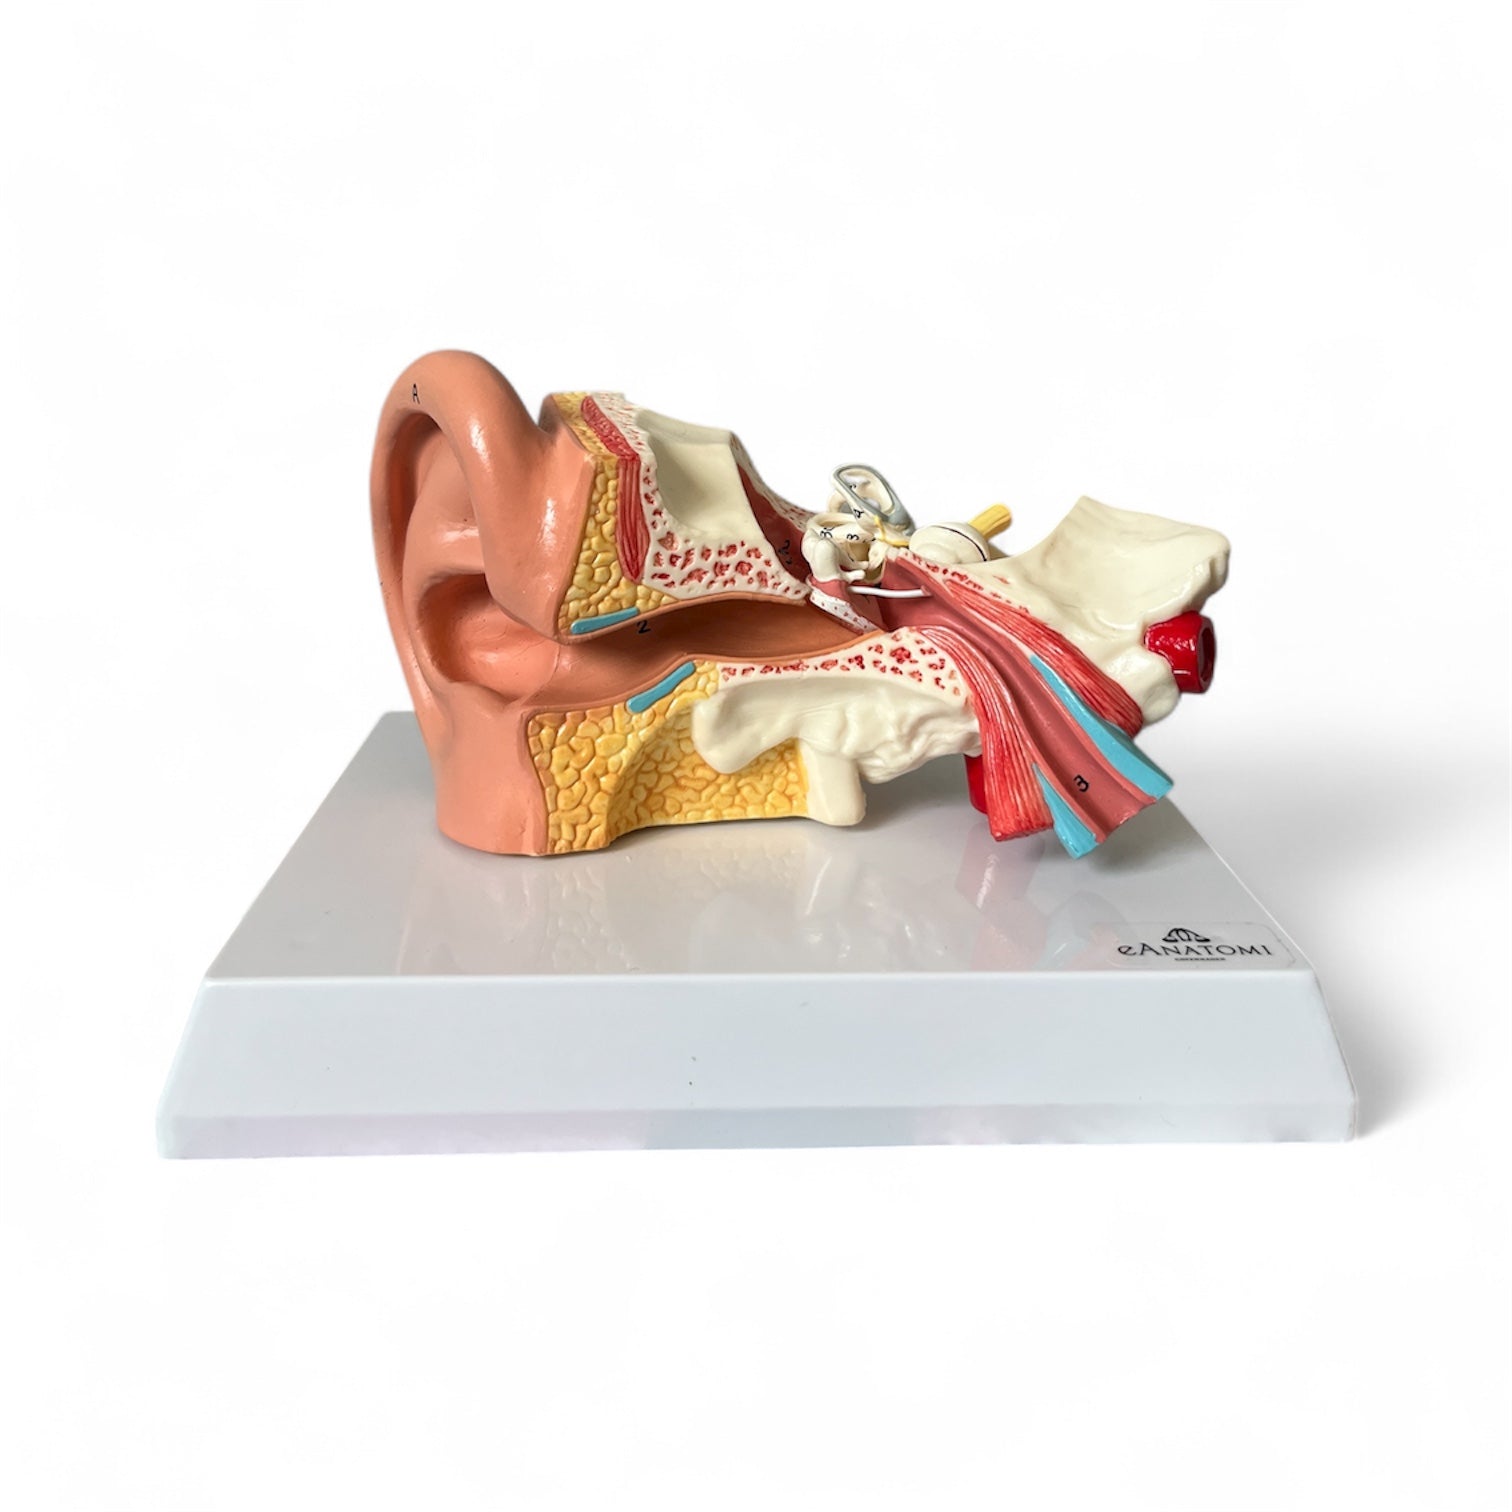

Selling anatomical models is the mainstay of eAnatomi, although we also spend a lot of resources developing our own anatomical materials such as posters. Anatomical models are used for various purposes and can show both defined tissues, organs and organ systems. Are you looking for a simple model of bone tissue or perhaps an advanced torso model based on MRI technology, you can find it all at eanatomi.com.